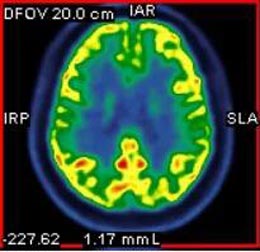

经过检查,李花发现小文左侧颞叶内侧局灶性脑皮质发育不良,幕上轻度弥漫性脑萎缩。颞叶病变很容易引起癫痫的发作。随后的长程视频脑电图也显示小文左后头部有癫痫样放电。最终李花明确诊断,小文是癫痫。

▲患者PET-CT